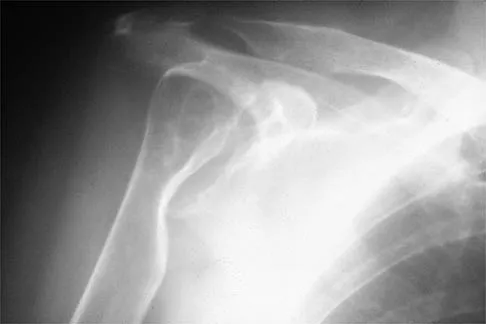

Figures 10a and 10b show the radiographs of a 47-year-old man who reports pain in both shoulders. He has a history of leukemia that was treated with chemotherapy and high-dose cortisone. What is the most reliable treatment option for pain relief in this patient?

Explanation

The radiographs reveal osteonecrosis with collapse. The most reliable and durable treatment for osteonecrosis of the humeral head remains prosthetic shoulder arthroplasty. Osteonecrosis of the humeral head may be seen after the use of steroids, and there is an increasing demand for shoulder arthroplasty in young people because of the use of high-dose steroids in chemotherapy regimes for the treatment of malignant tumors. The indications for most shoulder arthrodeses today include posttraumatic brachial plexus injury, paralytic disorders in infancy, insufficiency of the deltoid muscle and rotator cuff, chronic infection, failed revision arthroplasty, severe refractory instability, and bone deficiency following resection of a tumor in the proximal aspect of the humerus. Clearly, the role of arthroscopy and related minimally invasive techniques in the treatment of humeral head osteonecrosis remains unknown. Hasan SS, Romeo AA: Nontraumatic osteonecrosis of the humeral head. J Shoulder Elbow Surg 2002;11:281-298. Hattrup SJ: Indications, technique, and results of shoulder arthroplasty in osteonecrosis. Orthop Clin North Am 1998;29:445-451.